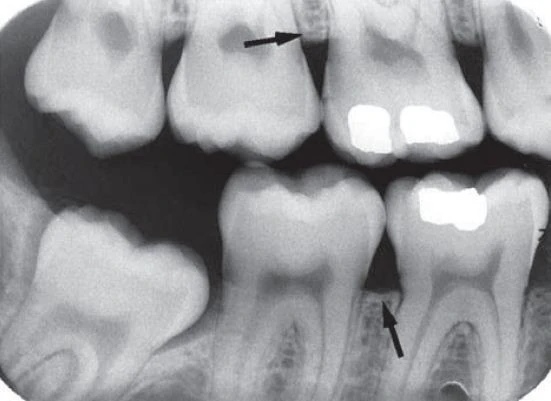

Đọc tiếpPhim cánh cắn luôn là công cụ đắc lực giúp chẩn đoán sâu răng mặt bên, và còn gì nữa?…